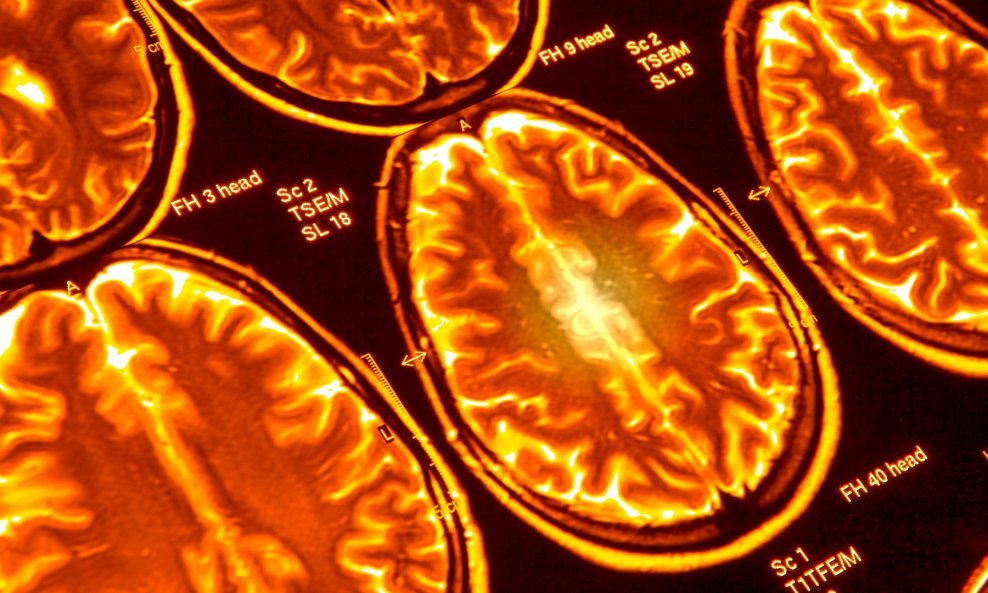

Najnovija studija uz pomoć umjetne inteligencije nastoji otkriti fizičke razlike između mozgova konzervativaca i liberala

Prema najnovijoj studiji, znanstvenici su promatrali i snimali funkcionalnu povezanost mozgova 174 zdravih mladih odraslih osoba pri vršenju raznih jednostavnih zadataka poput čim bržeg stiskanja iskačuće tipke u zamjenu za novčanu nagradu, uparivanje imena s licima ili odgovaranja na pitanja oko pročitane priče odgovorima istina/neistina. Subjektima su mozgovi također skenirani tijekom odmora - dok su bili budni i opušteni uz zatvorene oči.

Mjerenje funkcionalne pvezivosti (FP) je relativno rijetka praksa u političkoj neuroznanosti. FP referira na načine kojima razni dijelovi mozga mogu istovremeno prikazati slične aktivnosti kao da međusobno komuniciranju. Istražitelji su iskoristili tehniku dubokog učenja podi imenom BrainNetCNN koja radi na superračunalima u centru u Ohiju kako bi analizirali funkcionalnu povezivost podataka raznih zadataka te ih povezala sa subjektovom političkom ideologijom koja se mjeri u skali od jedan do šest (od vrlo liberalan do vrlo konzervativan).